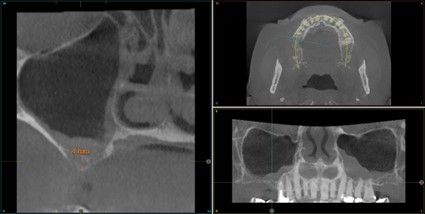

Resultados. Fueron reclutados 13 pacientes en los que se insertaron 30 implantes. Una vez insertados y cargados los implantes, la altura media final fue de 9,68 mm (+/- 2,66), lo que supone una ganancia promedio de 5 mm. A los 10 años, se observó una disminución media de la altura ósea ganada en los implantes en conjunto de 0, 29 mm (+/- 0,77). La media de la pérdida ósea mesial fue de 0,73 mm (+/- 0,75 mm) y la media de la pérdida ósea distal fue de 0,98 mm (+/- 1,2 mm). La supervivencia fue del 100%.

Results.Thirteen patients were recruited and 30 implants were inserted. Once the implants were inserted and loaded, the mean final height was 9.68 mm (+/- 2.66), which represents an average gain of 5 mm. At 10 years, there was a mean decrease in the overall bone height gain of the implants of 0.29 mm (+/- 0.77). The mean mesial bone loss was 0.73 mm (+/- 0.75 mm) and the mean distal bone loss was 0.98 mm (+/- 1.2 mm). Survival was 100%.

Nuestro grupo de estudio modifica esta técnica de elevación transcrestal utilizando para el acceso unas fresas de corte frontal que permiten eliminar la cortical inferior del seno con lentitud sin dañar la membrana de Schneider, eliminándose los osteotomos y el malestar que genera su accionamiento mediante el martillo6-7. Inicialmente el procedimiento fue concebido para ser empleado con material de injerto al igual que el abordaje convencional, pero posteriormente se presentaron variaciones del procedimiento donde se insertaban los implantes sin injerto, utilizándose el propio implante como mantenedor de espacio entre la membrana de Schneider y la cavidad creada entre la membrana y la cresta, permitiendo que esta cavidad no se colapsase y posteriormente fuera colonizada por nuevo hueso7-11.

Los senos tratados con la técnica de elevación transcrestal sin material de relleno muestran un incremento de entre 2,5 mm12,13 hasta 4.4 mm14,15 en la altura ósea lograda sobre el ápice y una supervivencia de los implantes que se sitúa entre un 94 y un 100%16-17. En este trabajo se presenta un estudio retrospectivo donde se ha evaluado la inserción de implantes extracortos (5,5 y 6,5 mm) en zonas posteriores maxilares mediante la técnica de elevación de seno transcrestal con la fresa de ataque frontal sin la utilización de material de injerto, con un tiempo de seguimiento de 10 años para poder objetivar el comportamiento de los implantes a largo plazo y de la técnica empleada.